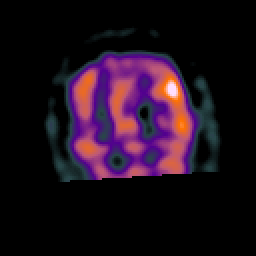

Subacute Stroke, overlay -- Slice #20

[Home][Help][Clinical] Slice 20